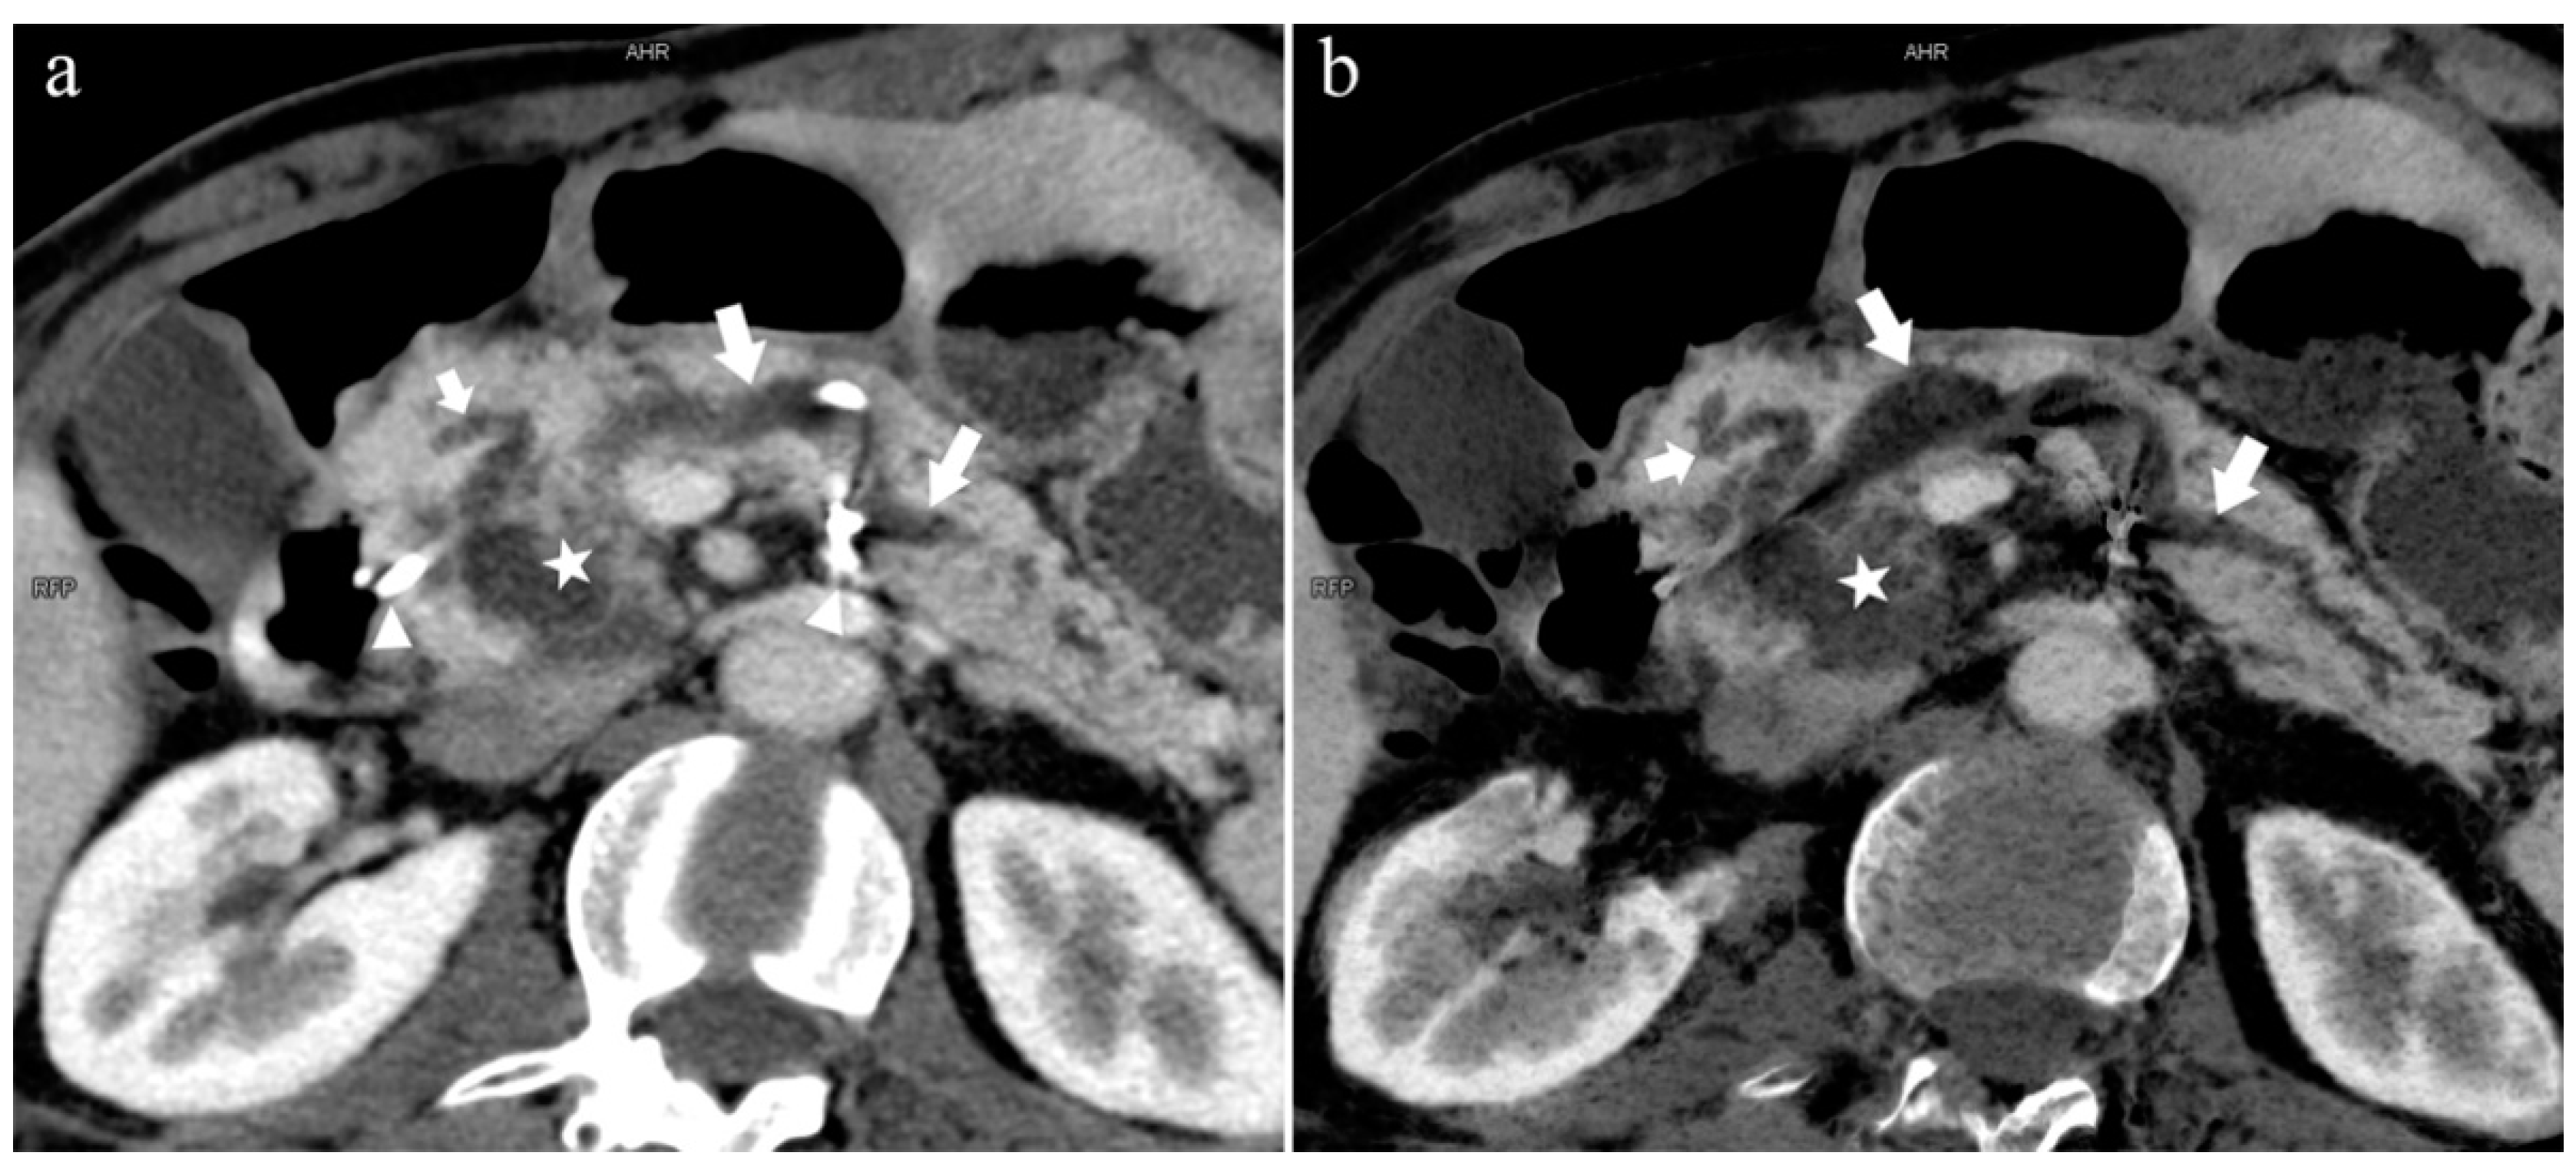

Figure 9.

Type 3a. A 49-year-old male patient with IPMN. (a): MIP [45 keV MEI (+)] shows the enlarged head of the pancreas with tumor (pentagram), and tortuous dilation of MPD (long arrow) and APD (short arrow). The APD communicates with the front segment of the MPD without flowing into the MiP. The drainage tube (arrow) can be seen in the MPD. (b): MinIP [45 keV MEI (+)] reduces the interference of ductal artifacts and shows the course and more detail of the distal pancreatic duct. Postoperative pathology confirmed that the mass was IPMN.